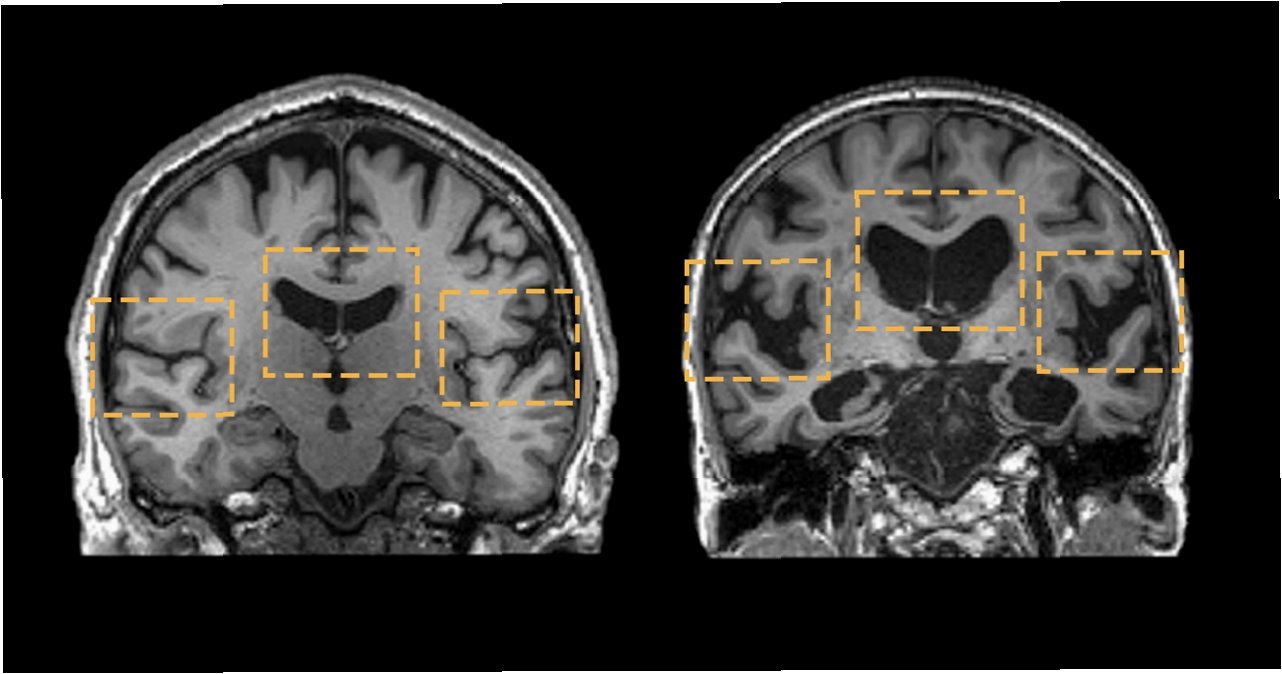

간과 뇌, 생각보다 가까운 사이

간은 뇌 건강에도 중요한 영향을 미칩니다. 간 기능 부전은 혈액 내 독성 물질의 증가를 유발하고, 이는 뇌 기능 저하, 기억력 감퇴, 심지어 뇌 질환으로 이어질 수 있습니다. 간성 뇌증은 간 질환의 심각한 합병증 중 하나로, 뇌 기능에 심각한 영향을 미칩니다. 뇌 건강을 위해서는 간 건강 관리가 필수적이며, 간 건강을 위해서는 뇌 건강에 유해한 생활 습관을 개선해야 합니다. 스트레스 관리, 충분한 수면, 건강한 식습관은 간과 뇌 모두에 긍정적인 영향을 미칩니다.